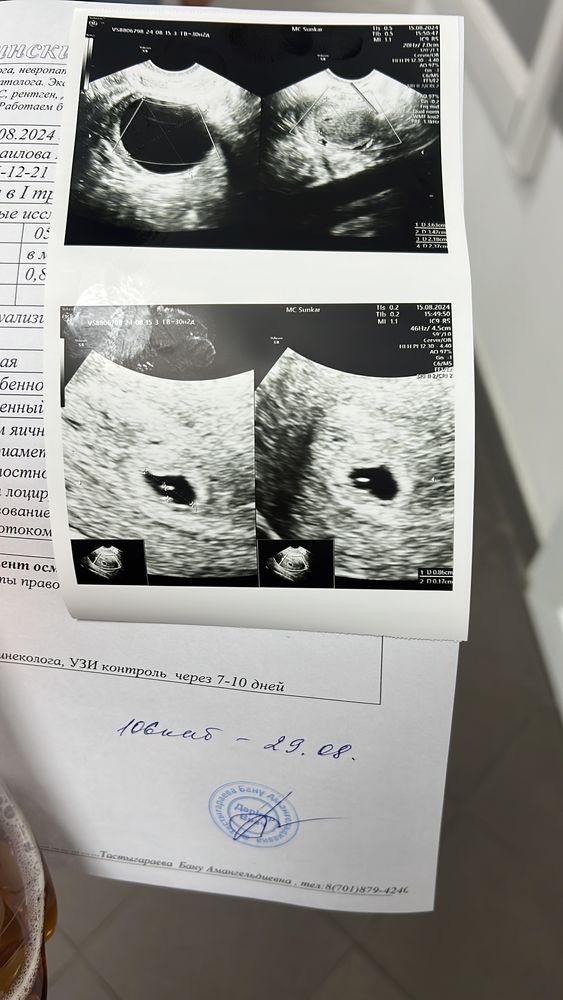

УЗИ на 6 неделе

Анализы, скринингиДевочки все хорошо беременность маточная , сказали овуляция была поздняя, А ещё чему удивился врач то что была овуляция аж в двух яичниках. Срок сказали что пока недельки 4. Есть киста в правом яичнике, пока не понятно киста желтого тела. Сказали контрольно через 2 недели прийти , но думаю больше ходить не буду пойду только уже на плановое узи